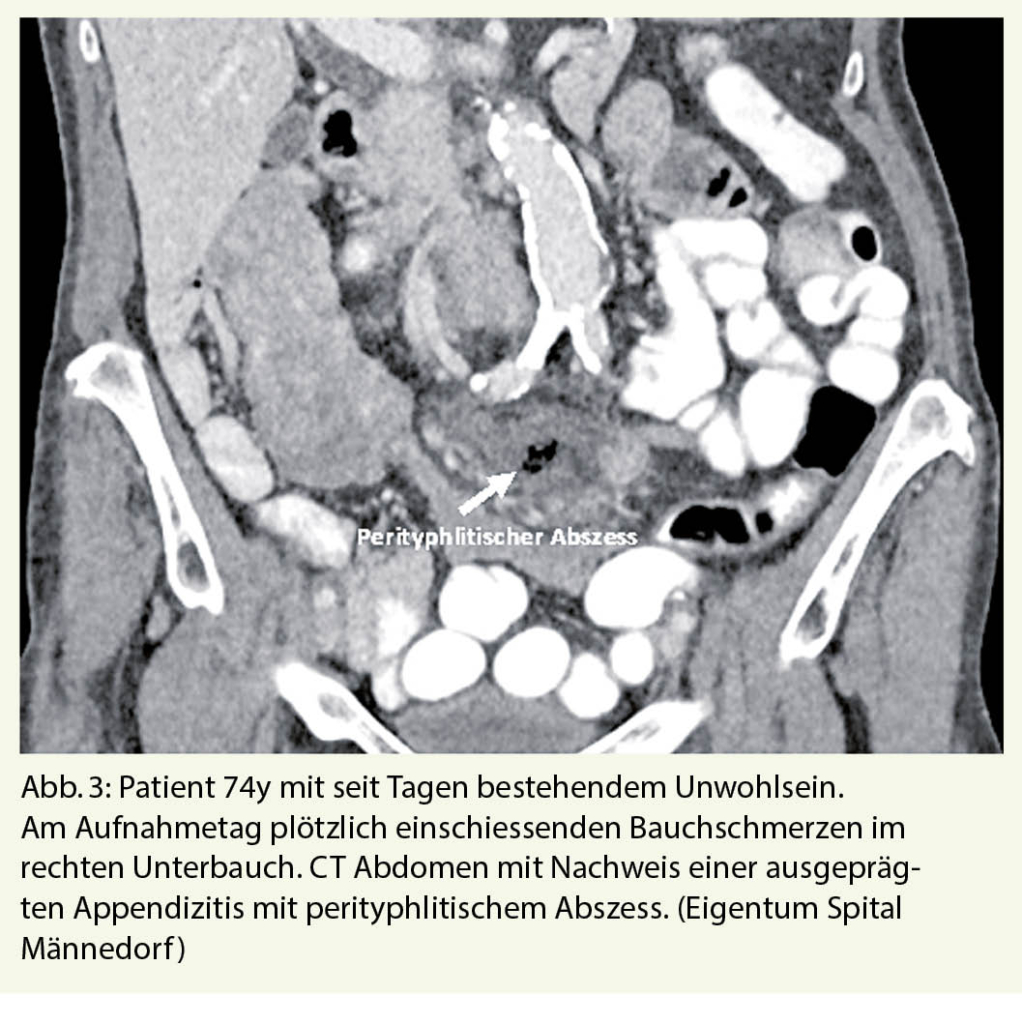

Akute Appendizitis

Die akute Appendizitis ist bei älteren Patienten mit akuten Bauchschmerzen seltener als bei jüngeren Patienten, wobei allerdings Morbiditäts- und Mortalitätsraten höher sind (Abb.3). Zwischen 5 und 10 % der Fälle von Appendizitiden treten bei Menschen über 65 Jahren mit einer Mortalität von 10-20 % und einer Morbidität von 30-60 % auf. Dafür ursächlich sind alterstypische Komorbiditäten sowie häufig eine Therapieverzögerung durch atypische Symptome mit dadurch bedingt höherer Perforationsrate (9, 10).